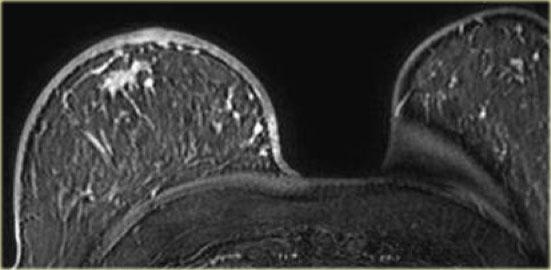

Hình ảnh ngoài cùng bên trái là u xơ tuyến vú dạng trẻ em (juvenile fibroadenoma) – có hình bầu dục với bờ nhẵn, tức là đặc điểm điển hình của tổn thương lành tính.

Các vách ngăn không ngấm thuốc không được thấy trong trường hợp này.

Hình ảnh bên phải là một ví dụ khác về u xơ tuyến vú: khối dạng thùy múi với các vách ngăn không ngấm thuốc.